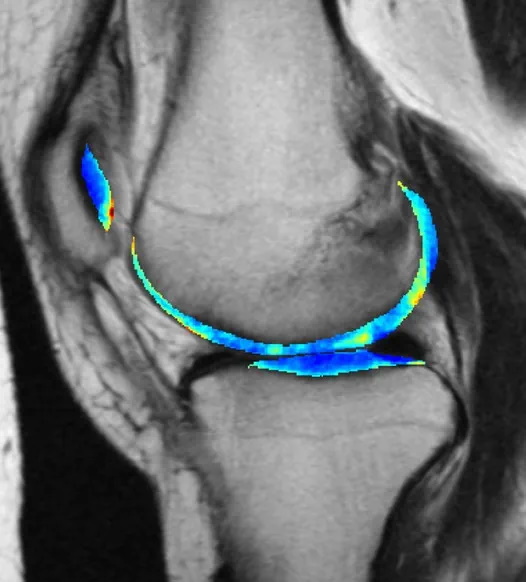

El modelo ML detecta la artritis temprano

Créditos de imagen: UC San Diego

Uno de los casos de uso más confiables del aprendizaje automático es entrenar un modelo en un patrón de destino, por ejemplo, una forma particular o señal de radio, y soltarlo en una gran cantidad de datos ruidosos para encontrar posibles resultados que los humanos podrían tener dificultades para percibir. Esto ha demostrado ser útil en el campo de la medicina, donde los primeros indicios de afecciones graves pueden detectarse con suficiente confianza para recomendar más pruebas.

Este modelo de detección de artritis analiza las radiografías, al igual que los médicos que realizan ese tipo de trabajo. Pero cuando es visible para la percepción humana, el daño ya está hecho. Un proyecto de larga duración que siguió a miles de personas durante siete años resultó en un gran conjunto de entrenamiento, haciendo visibles los primeros signos casi imperceptibles de la osteoartritis en el modelo de IA, que lo predijo con un 78% de precisión en tres años.

La mala noticia es que saberlo temprano no significa necesariamente que se pueda evitar, ya que no existe un tratamiento eficaz. Pero ese conocimiento se puede utilizar para otros usos, por ejemplo, pruebas mucho más efectivas de potencial tratos. “En lugar de reclutar a 10,000 personas y seguirlas durante 10 años, podemos simplemente inscribir a 50 personas que sabemos que van a tener osteoartritis … Luego podemos darles el medicamento experimental y ver si detiene el desarrollo de la enfermedad”, dijo el co -autor Kenneth Urish. El estudio apareció en PNAS.